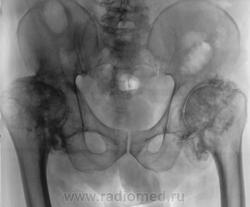

"Спинальный больной". Наблюдение Бородулина М.А. Наблюдение Бордулина М.А. Наблюдение Катенёва В.Л. Пт, 06/07/2012 - 21:41 #1 Наталия Васильевна Не на сайте Был на сайте: 5 лет 7 месяцев назад Зарегистрирован: 25.09.2011 - 09:02 Публикации: 754 А возможны ли такие изменения при сирингомиелии? Пт, 06/07/2012 - 22:22 #2 Катенёв Валенти... Не на сайте Был на сайте: 6 лет 11 месяцев назад Зарегистрирован: 22.03.2008 - 22:15 Публикации: 54876 По всей видимости - да. Пт, 06/07/2012 - 23:03 #3 И.Бондаренко Не на сайте Был на сайте: 1 день 9 часов назад Зарегистрирован: 13.09.2011 - 22:55 Публикации: 9199 Считайте ,что такие изменения сопутствуют сирингомиелии. Пт, 06/07/2012 - 23:08 #4 Катенёв Валенти... Не на сайте Был на сайте: 6 лет 11 месяцев назад Зарегистрирован: 22.03.2008 - 22:15 Публикации: 54876 И.Бондаренко wrote: Считайте ,что такие изменения сопутствуют сирингомиелии. +1 Сб, 07/07/2012 - 22:10 #5 Наталия Васильевна Не на сайте Был на сайте: 5 лет 7 месяцев назад Зарегистрирован: 25.09.2011 - 09:02 Публикации: 754 Ну, тогда, действительно-"спинальный больной".

А возможны ли такие изменения при сирингомиелии?

По всей видимости - да.

Считайте ,что такие изменения сопутствуют сирингомиелии.

Ну, тогда, действительно-"спинальный больной".